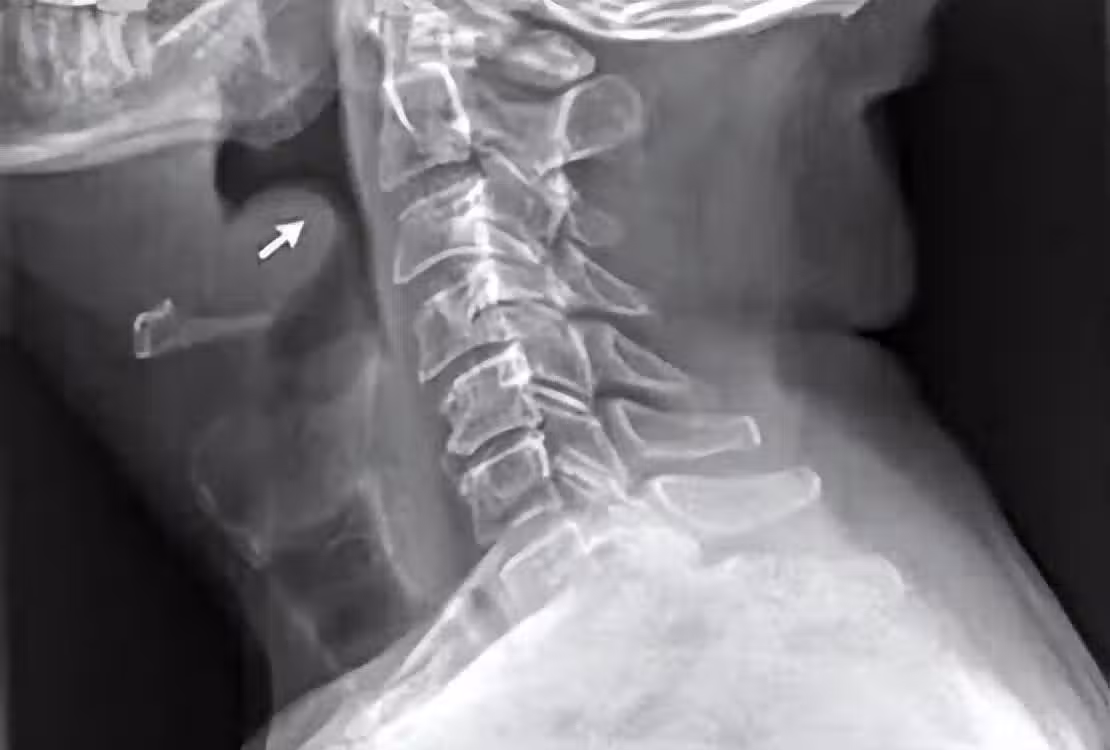

會厭處於舌根後方,一般我們進食時食物會經過咀嚼形成球狀,此時會厭自動關閉,防止食物進入肺部。可一旦會厭發炎,就可能堵塞呼吸道,這時就會呼吸困難。